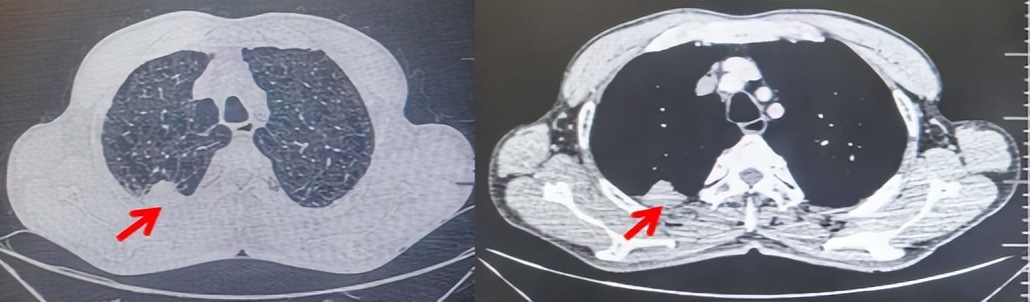

2024.11.19患者出现右侧胸痛,复查胸部CT检查示右侧胸膜肿物,大小约31mmX24mm,右侧4、5肋骨骨质破坏,考虑转移(如图2)。建议患者穿刺活检取病理明确诊断,患者拒绝,经MDT会诊后结合影像学表现及病史考虑为胸膜转移,肋骨转移,分期为rT0N0M1a IVA期,DFS仅仅17个月。2024.12.05起行信迪利单抗联合培美曲塞+卡铂方案治疗4周期,复查胸CT评效PR(如图3)。之后给予信迪利单抗+培美曲塞维持治疗6周期,期间复查CT评效PR(如图3)。目前信迪利单抗+培美曲塞维持治疗中,截止至目前PFS约为8个月,治疗期间未出现明显毒副反应。

图2:患者胸膜及肋骨转移(2024.11)胸部CT肺窗、纵隔窗及骨窗

71岁男性,高血压病史20年,口服药物治疗,无糖尿病、心脏病等基础疾病,吸烟史50年,20支/天,已戒1年余,无饮酒史,无肿瘤家族史。2023.11因咳嗽、咳痰行胸CT检查:左肺下叶占位性病变,大小约12mmx8mm(如图5)。2023.11.20行“单孔胸腔镜左肺中下叶切除、肺门及纵隔淋巴结清扫、胸膜粘连松解术”;术后病理:(左肺下叶)结合免疫组化鳞状细胞癌(中、低分化),局部见脉管内癌栓,未见确切神经侵犯,(气管切缘)净。(淋巴结)未见转移癌0/19(4组0/1;5组0/1;6组0/2;7组0/1;9组0/1;10组0/2;11组0/3;12组0/2;13组0/2;14组0/4)。术后分期pT1bN0M0 IA期,术后定期复查。

2024.09.12复查胸部CT示左侧胸膜结节,大者约为27mmx13mm,考虑转移可能性大,纵隔淋巴结增大,恶性?(如图6)。患者行胸膜穿刺活检取病理,结果示(胸膜)结合免疫组化,支持鳞状细胞癌,PD-L1(克隆号28-8)TPS约20%。分期为rT0N2bM1a IVA期,DFS为10个月。2024.09.24起行替雷利珠单抗联合紫杉醇+卡铂方案治疗4周期,复查胸CT评效SD(如图7)。后患者因脑梗塞停止治疗,于综合医院就诊,后未返院复查及治疗。

图5:患者手术前(2023.11)胸部CT肺窗及纵隔窗

图6:患者胸膜及纵隔转移(2024.09)胸部CT肺窗及纵隔窗